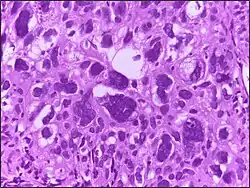

![]() |

Tumor giant cell | Malignant neoplasm showing marked anaplasia. Note the marked nuclear pleomorphism, bizarre cells and tumor giant cells. | Category: Histopathology of giant cell tumors | Giant cell tumor |